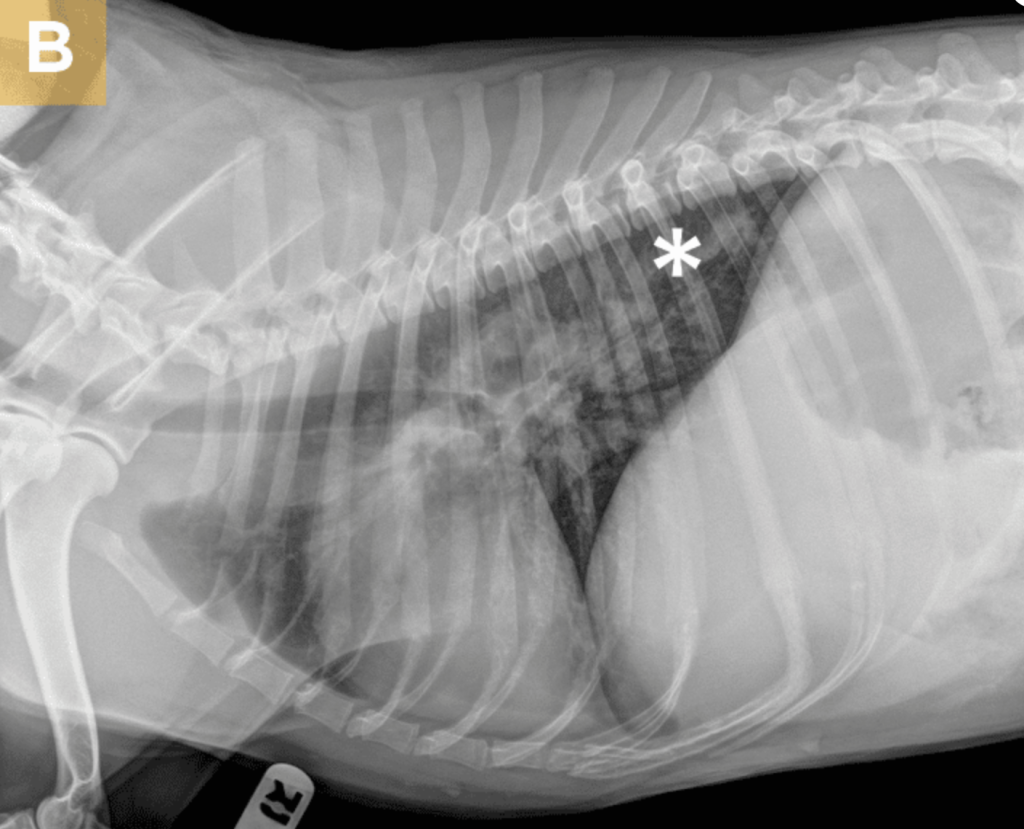

肺动脉高压间接由右心室肥大(腹侧/背腹侧视图上的“倒D”)、主肺动脉扩张(同一视图上1点钟位置的隆起)和分支肺动脉扩张(有或无截断和迂曲)支持(图1)。肝肿大和腹水(头腹部浆膜细节缺失)的发现支持右侧心力衰竭。支持肺血栓形成/栓塞的结果包括间质合并至肺泡浸润,尤其是在肺尾叶;合并证据;和区域性血过少。